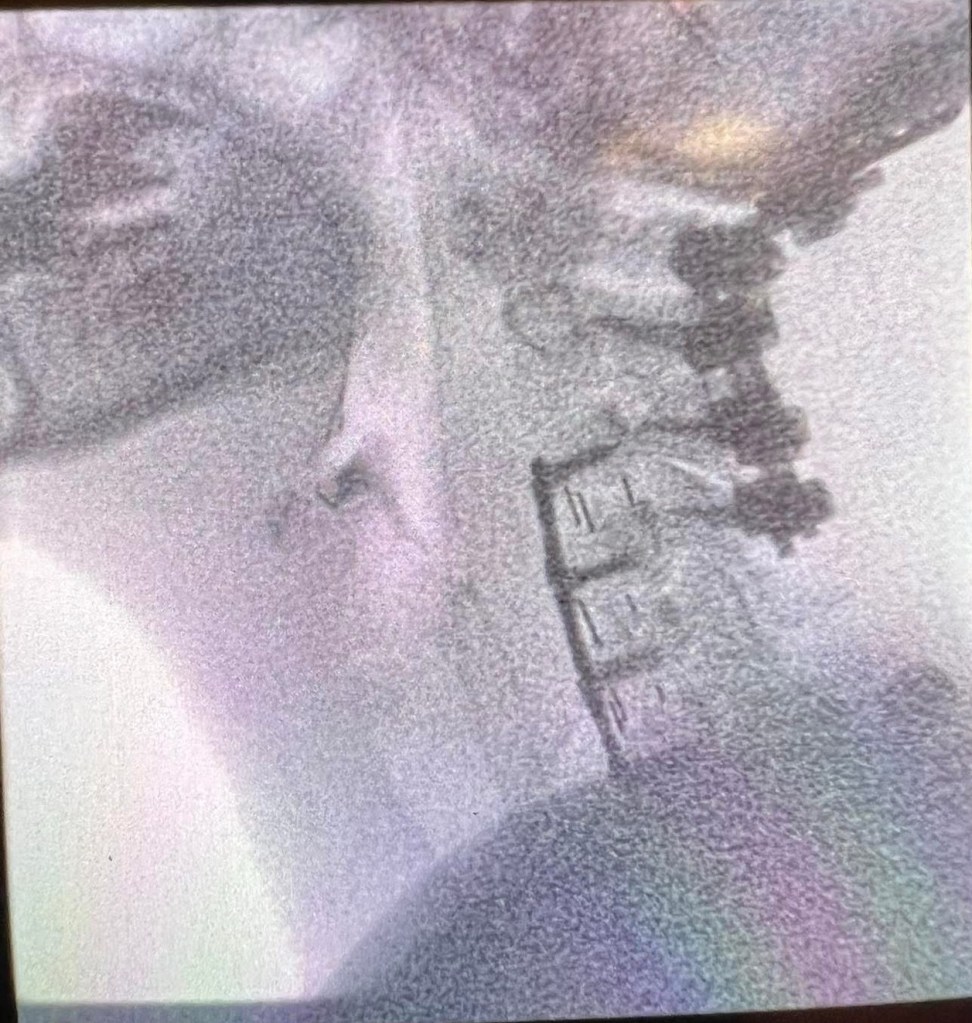

At age 31, I was diagnosed with craniocervical instability (CCI) and at age 32, I began the journey of fusion, to stabilize my spine. Between 32-33, I had 3 cervical spine surgeries, where I ended up fused from skull-C4, and 2 lumbar spine surgeries, due to tethered cord syndrome.

At age 33, I seemed to regain some functionality and the day before I turned 34, I was able to RUN an entire 5k. I trained so hard and I accomplished my goal. The significance being, that I almost died from a post-op infection on my 33rd birthday. So running that 5k, one year after that, meant everything to me. However, 6 days after the 5k, I fell and tore my ACL, MCL, calf muscle, and meniscus in my left knee and required another surgery to repair the damage. And it wasn’t long after that knee surgery, that I fell again and damaged my cervical fusion. So at age 34, I had 2 more cervical spine surgeries that left me fused from skull-C6.

Unfortunately, I know this is not the end. My skull-C6 fusion isn’t fused in some places and is collapsing in other places. After spending over 2 years trying to find a neurosurgeon to take my case and being thrown around like a hot potato, I am finally a Mayo Clinic patient and I have an appointment in August, to meet with the complex spine surgeon and discuss surgical options. There will be more cervical spine surgeries in my very near future, that will hold greater risks than any of my previous surgeries. I will likely reach 45 surgeries, before I even turn 40 years-old. All this time, I’ve been desperate to return to my life as I knew it, but I’ve begun to realize that, that life is long gone. That part of my life has come to an end; but this part of my life is only beginning. The hell that I have been through and that I’m still going through has given me a very unique set of knowledge, experience, and skills, that allows me to be a powerful advocate for other chronically ill or disabled folks. Healthcare shouldn’t be like this. I deserve better. You deserve better. We all deserve better. Our lives are worth more than a payday for billionaires.